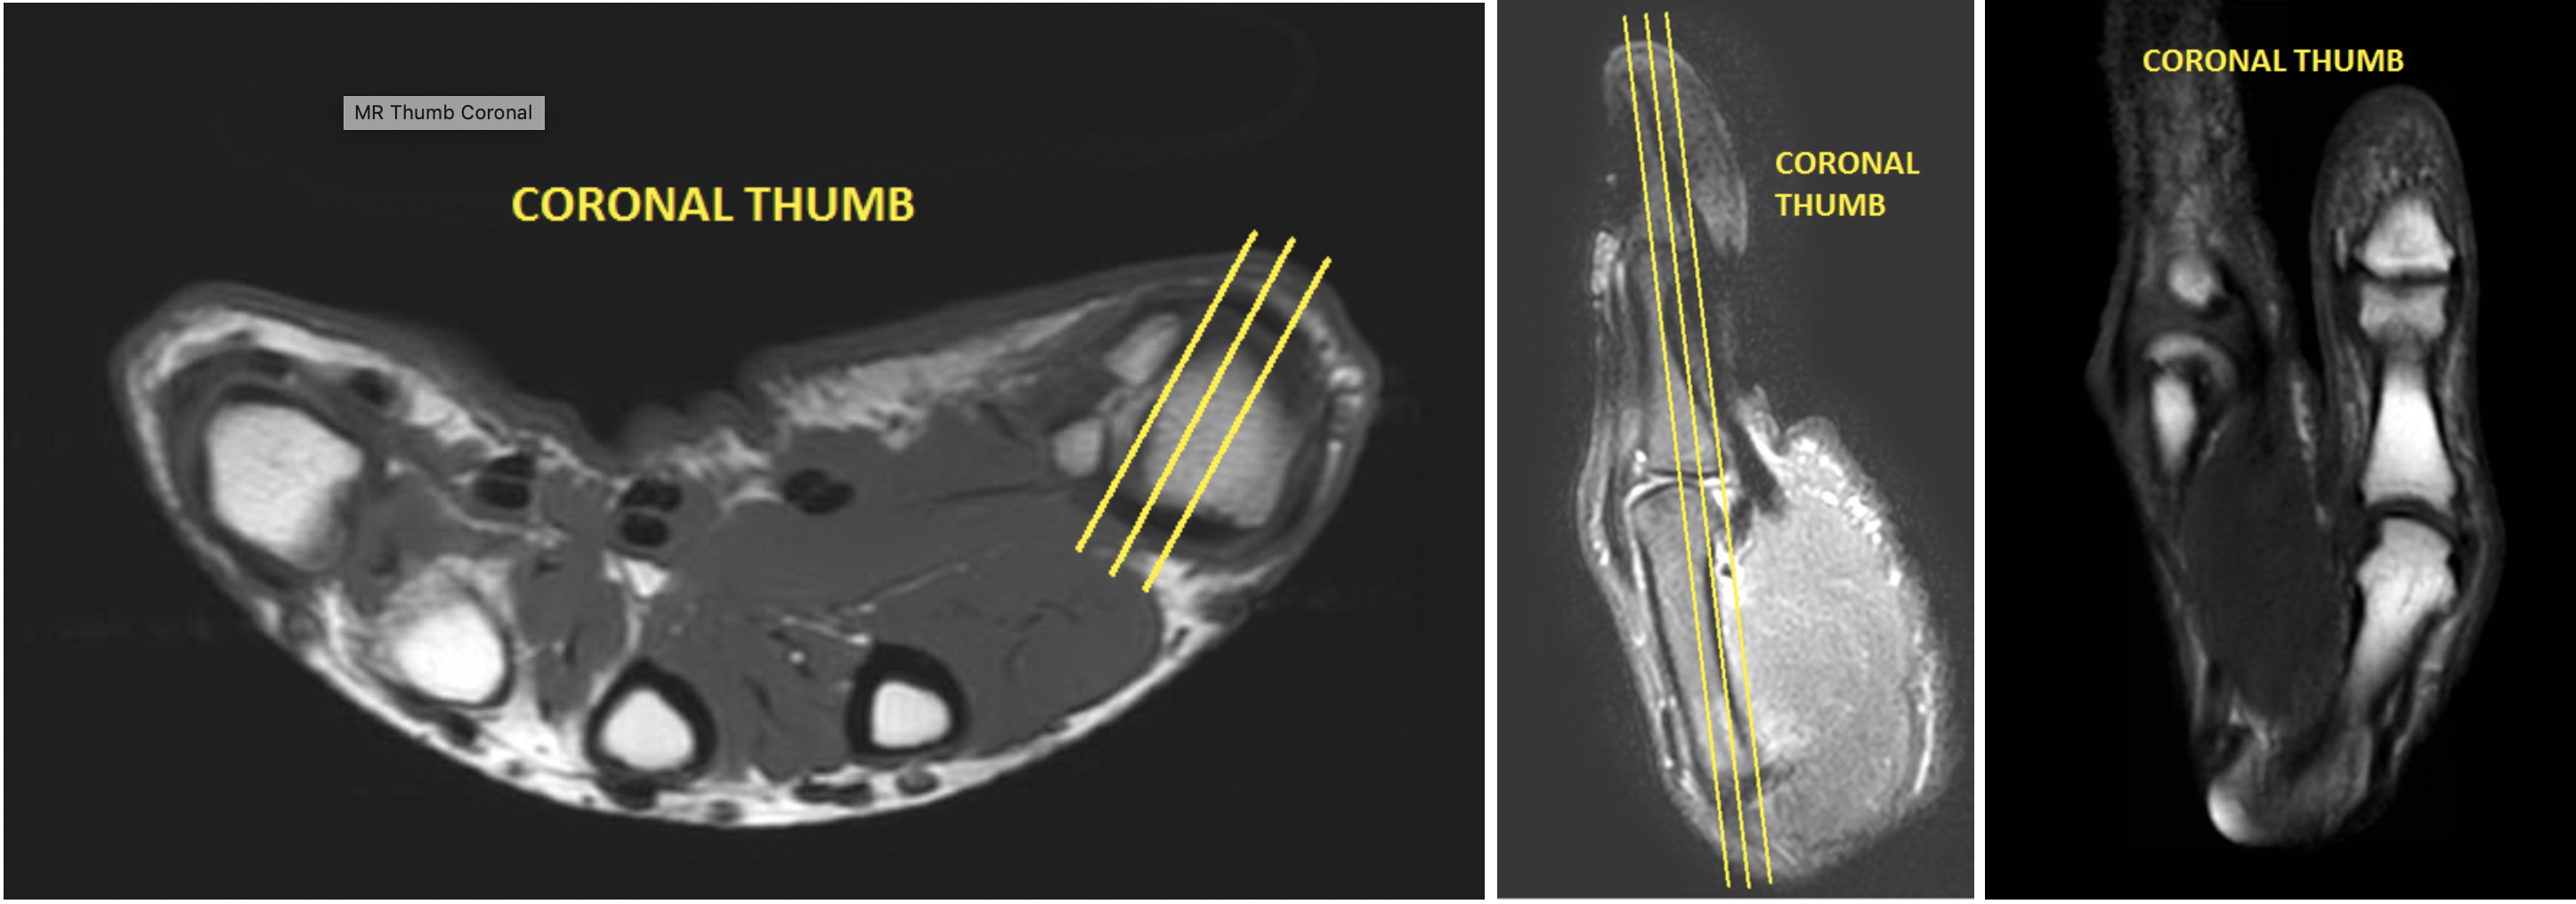

| COR | T1 | TSE | 3mm | 0.5mm | None | 12cm | Angle relative to Radio-Ulnar joint |

| COR | Mid TE (40-50) T2 Fat Sat | TSE | 3mm | 0.5mm | SPAIR | 12cm | Angle relative to Radio-Ulnar joint |